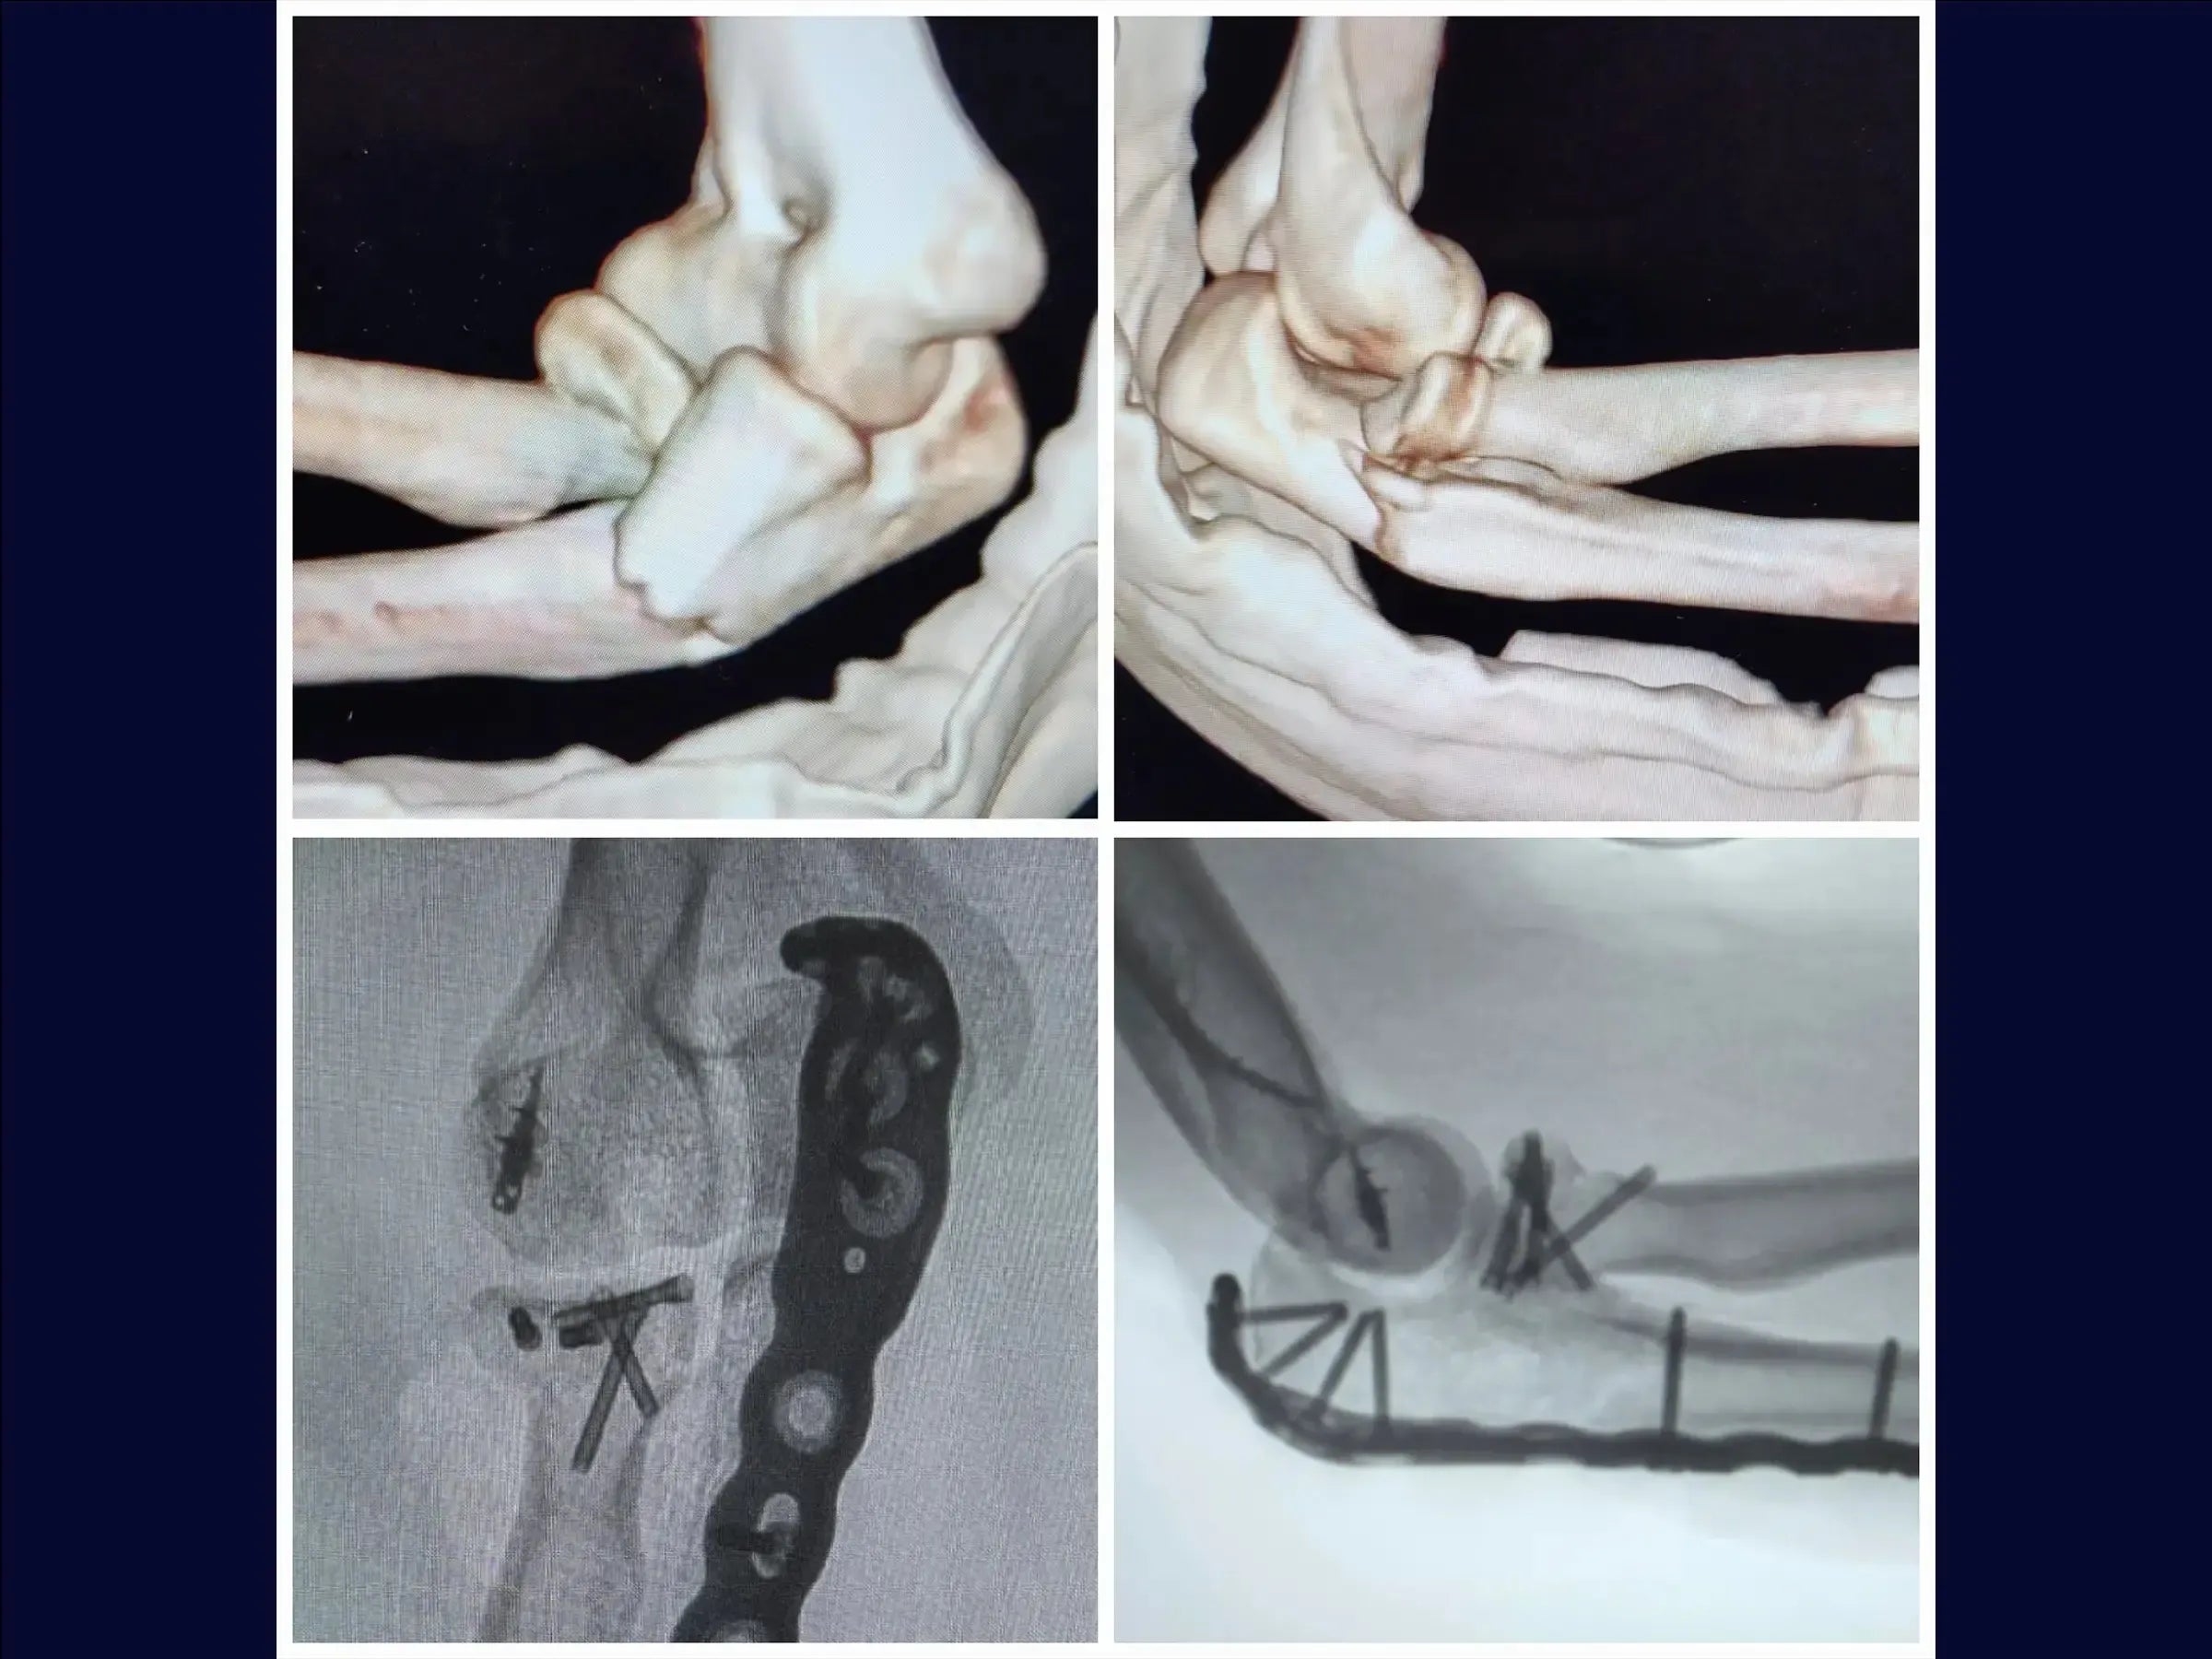

Fractura metafisaria del cúbito proximal con luxación y fractura de la cabeza radial (variante de Monteggia)

Mejore sus habilidades en el tratamiento de una de las lesiones de codo más complejas: la fractura metafisaria del cúbito proximal asociada a la luxación posterior y la fractura de la cabeza radial, conocida como variante de Monteggia . Esta formación abarca la reducción anatómica del cúbito y la cabeza radial, la fijación con placas y tornillos, y la reinserción de estructuras ligamentosas, con el objetivo de restaurar la estabilidad articular y permitir la movilidad temprana del codo, minimizando el traumatismo tisular y optimizando el resultado estético.

- Tratamiento quirúrgico de la fractura metafisaria del cúbito proximal con luxación posterior y fractura de la cabeza radial ( variante de Monteggia ).

- Reducción anatómica del cúbito y la cabeza radial.

- Fijación estable con placas y tornillos.

- Fijación de la cabeza radial : Reducción manual con tornillos minifragmentarios en técnica de trípode con estabilidad subcondral .

- Reinserción de ligamentos : Anclaje metálico de 5,0 mm para una reinserción precisa de las estructuras laterales, garantizando la estabilidad de la articulación.